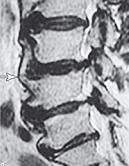

На рентгенограмме № 6 поясничного отдела позвоночника выраженный остеофитоз, спондилёз третьей степени, что также хорошо видно на МРТ № 39 поясничного отдела позвоночника МРТ № 40 ![]() МРТ № 41

На МРТ № 40 наблюдается типичный пример развития стеноза второго типа в шейном отделе позвоночника. И аналогичная картина, только, в поясничном отделе позвоночника, отображена на МРТ № 41 Стеноз Стеноз позвоночного канала встречается довольно часто, во всяком случае в моей практике. В данной книге я уже упоминал о том, что стеноз спинномозгового канала (то есть его сужение) может вызывать серьёзные осложнения при течении таких заболеваний, как например, грыжи межпозвонкового диска. Для лучшего понимания происходящих процессов давайте в общих чертах рассмотрим, что такое стеноз и чем он опасен. Итак, стеноз — это врождённое или приобретённое аномальное сужение просвета какого-либо полого органа (пищевода, кишечника, кровеносного сосуда и др.) или отверстия между полостями (например, при пороках сердца). Стеноз позвоночного канала характеризуется его патологическим сужением. Исходя из анатомо-физиологических особенностей позвоночного канала, который является вместилищем и в тоже время охранным футляром для спинного мозга, даже незначительное его сужение может оказаться фатальным для спинного мозга. К примеру, при развитии абсолютного стеноза позвоночника спинной мозг может быть компримирован (сжат) вместе с артериями. В свою очередь это неизбежно ведёт к развитию ишемии (от греч. ischo — «задерживаю, останавливаю» и haima — «кровь»; уменьшение кровоснабжения участка тела, органа или ткани вследствие ослабления или прекращения притока к нему артериальной крови) тех участков спинного мозга, где блокировано кровоснабжение сдавленными сосудами. Ещё в конце XIX века, а точнее в 1880 году, в своей работе М. Литтен отметил, что спинной мозг более чувствителен к ишемическим повреждениям и недостатку кислорода, чем другие ткани организма. А вот отечественному невропатологу, ученику В. М. Бехтерева и одному из первых нейрохирургов, Л. М. Пуссепу в 1902 году удалось в эксперименте на животных показать, что даже непродолжительная ишемия спинного мозга влечёт за собой некроз (отмирание) нервных клеток передних рогов спинного мозга. Если добавить к этому ещё и неизбежное нарушение ликвородинамики и развития (вследствие сдавления оболочек спинного мозга) эпидурита и арахноидита, то возникновение болевых, корешковых и сосудистых синдромов (в виде миелоишемии, радикулоишемии или миелорадикулоишемии) становятся вполне объяснимыми и понятными. Исходя из классификации, предложенной доктором I. Stephen, которой пользуется большинство авторов в своих работах, стеноз позвоночного канала позвоночника, как я уже упоминал, бывает двух типов. Тип первый — врождённый, или как его ещё называют идиопатический, то есть беспричинный (неизвестного, неясного происхождения). Второй тип — приобретённый, возникший вследствие дегенеративно-дистрофических процессов в позвоночнике, посттравматический или обусловленный другими причинами, которые привели к стенозированию (сужению) позвоночного канала. Например, грыжа межпозвонкового диска даже центральной локализации, имеющая размер всего 6 мм в дорсальном направлении в поясничном отделе позвоночника с сагиттальным размером спинномозгового канала в 15 мм приводит к формированию абсолютного стеноза второго типа (приобретённого) и может вызвать серьёзные осложнения. А при стенозе первого типа (врождённого, см. МРТ № 43), к примеру с сагиттальным размером спинномозгового канала в поясничном отделе 12 мм, даже трёхмиллиметровая протрузия межпозвонкового диска может привести к развитию слабости в ногах, мышечной атрофии или, как описывал данные состояния Dejerine ещё в 1911 г., «перемежающейся хромоте спинальной природы». |